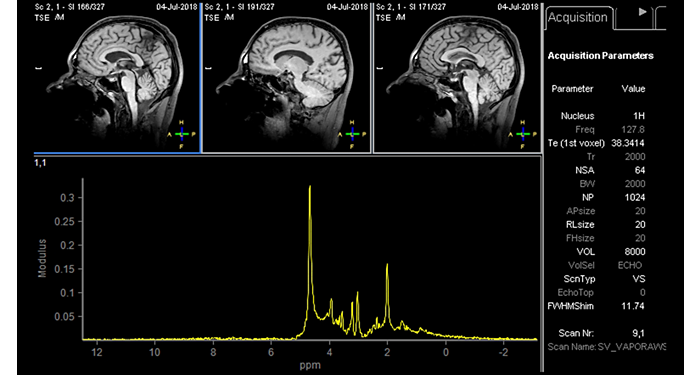

70% of radiologists consider neuro indications to be challenging, mostly due to a lack of appropriate imaging and visualization techniques¹. Philips aims to provide the best possible diagnostic clarity and treatment guidance for all patients with neurological disorders. By leveraging our dStream digital platform, this year, we are introducing, a set of novel imaging and visualization strategies. These may empower you to resolve complex neuro questions with more certainty, as well as unlock new neuro territories in advanced Neurofunctional applications. This is a key step towards elevating neuro diagnostics and ultimately touching more lives with MR imaging. ¹ TMTG Market Survey 2016

New neuro applications